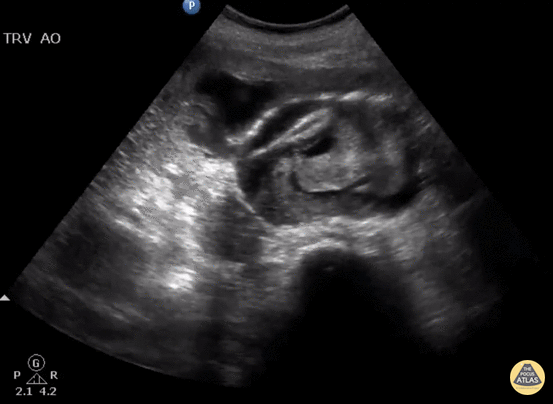

aortenaneurysma-u-ruptur